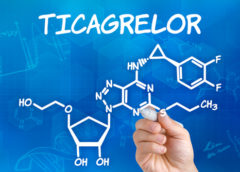

LeggiInversione del ticagrelor: esame in vitro di quattro agenti

La gestione delle emorragie indotte dal ticagrelor è difficoltosa in quanto le trasfusioni piastriniche risultano inefficaci, e sarebbe necessario sviluppare una strategia efficace. Un recente studio si è proposto di investigare l’efficacia in vitro di quattro farmaci emostatici. Ossia fattore VII attivato ricombinante (eFVIIa),…